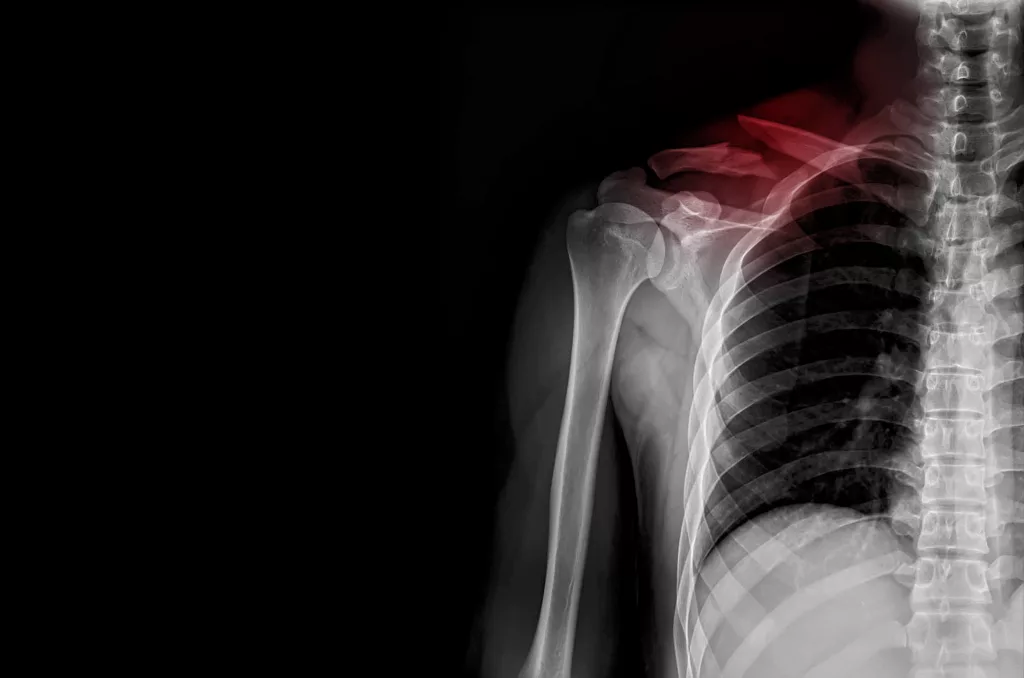

Traumatismes de l'épaule

• Fracture de la clavicule

• Fracture de l’extrémité proximale de l’humérus

• Disjonction acromio-claviculaire